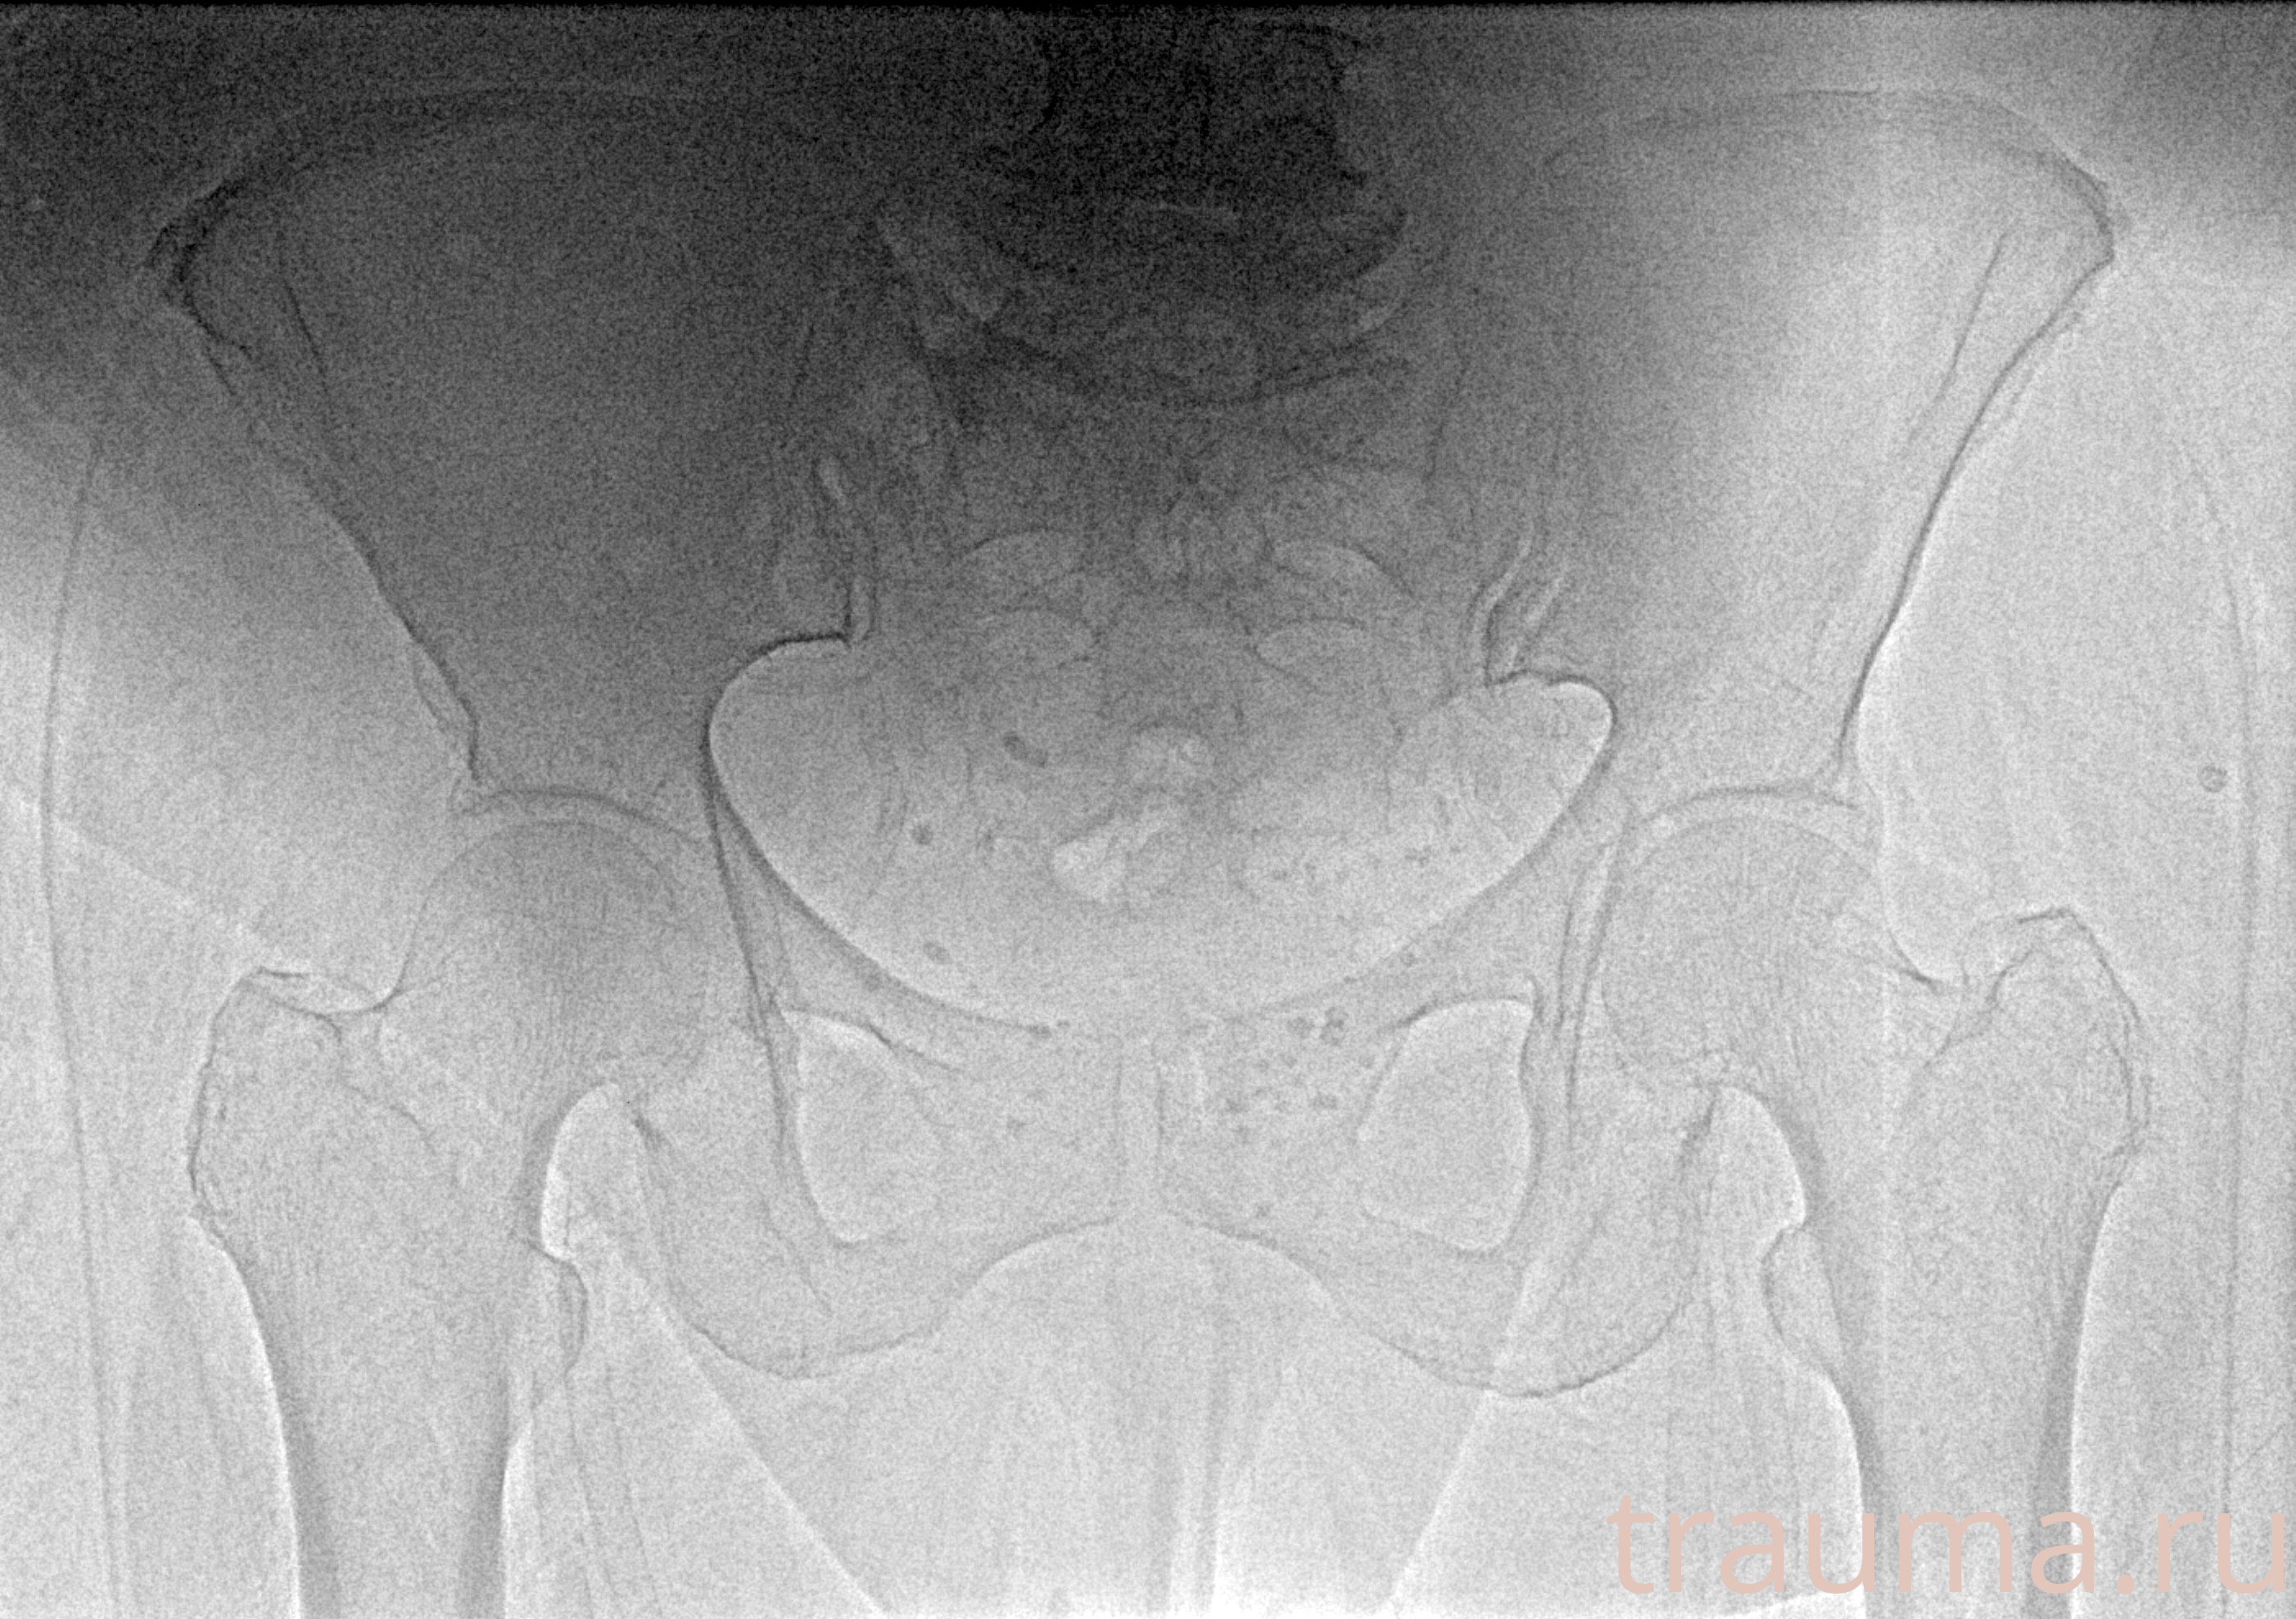

Рентгенограммы

Рентген на дому: по вашему адресу приезжает врач-рентгенолог, травматолог-ортопед с мобильным рентгеновским аппаратом, проводит диагностику травмы или заболевания, делает необходимые рентгенограммы, дает рекомендации по дальнейшему лечению. Получить качественные снимки в домашних условиях возможно благодаря уникальной методике, разработанной МосРентген Центром для института  Склифосовского

при переломе шейки бедра и пневмонии от компании МосРентген Центр - партнера Института имени Склифосовского